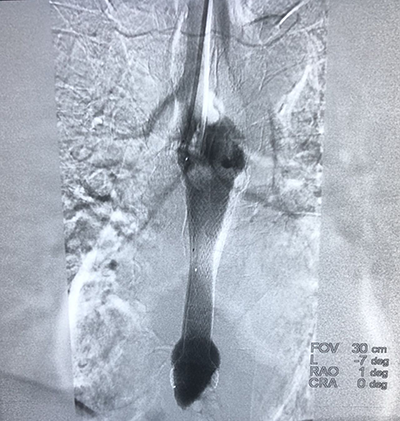

![]() | ![]() |

| (肺癌的介入治疗) | (盆腔恶性肿瘤的介入治疗) |